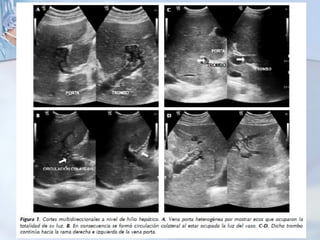

Pruebas de imagen:

Ecografía con eco-Doppler

TC

RMN.